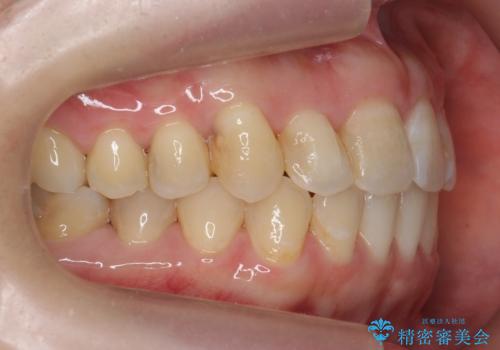

犬歯のねじれ 上の歯が引っ込んでいる

- 前歯の並びを気にして来院。

インビザラインで、上の前歯をやすり掛けして並べました。

途中妊娠、出産を挟み、患者様がアライナーがつけられない時期もあって治療自体は延長しました。